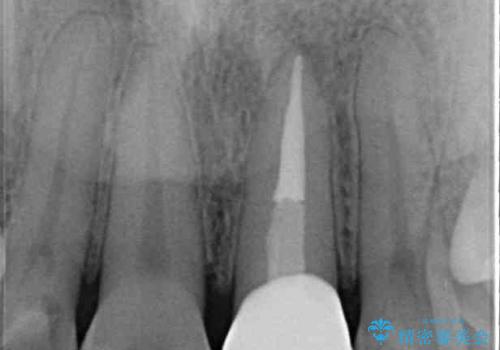

- 前歯のクラウン付近の歯肉が黒く見えることを気にして来院された患者様です。

根管治療を行った後に、オールセラミッククラウンにて補綴することとしました。